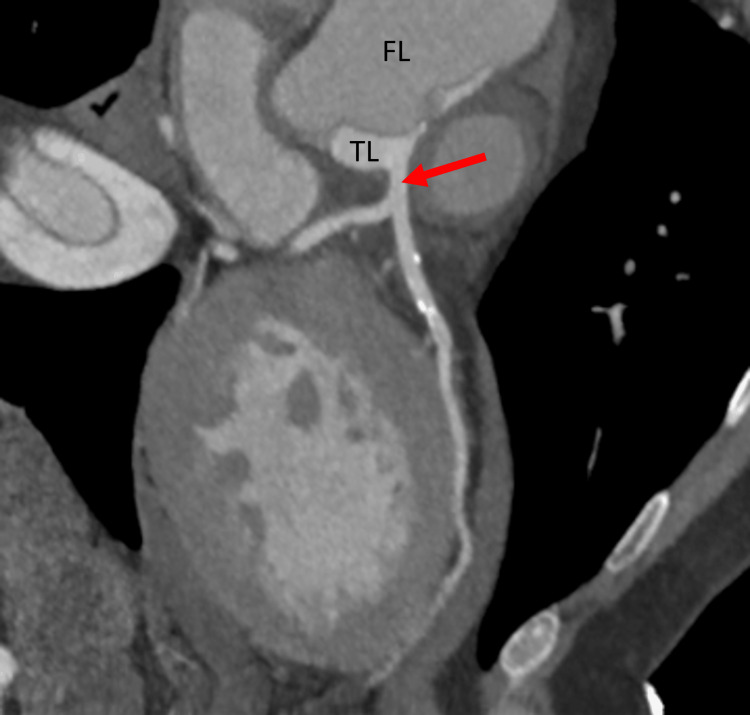

In view of chest pain associated with positive cardiac biomarkers, he was admitted to the Coronary Care Unit on intravenous nitroglycerin. While waiting for his admission, he suddenly had recurrent chest pain associated with marked hypotension (75/43 mmHg), for which the intravenous nitroglycerin was discontinued, fluid resuscitation was provided, and he was temporarily started on intravenous norepinephrine. The on-call cardiology team was contacted for an emergent evaluation. Subsequent ECG showed nonspecific ST-segment changes in leads V5-V6 (Figure 1). An emergent bedside echocardiogram revealed a moderate pericardial effusion of hemodynamic significance (Figure 2), as suggested by partial right ventricular chamber collapse (Figure 3) early in diastole and a plethoric non-collapsing inferior vena cava. The pericardial effusion also contained echogenic strands, which are highly concerning for blood clots. Additionally, a moderate to severe aortic valve insufficiency (Figure 4) was present according to color Doppler findings and pressure half-time assessment (315 ms). An intimal flap was visualized on the ascending and descending aorta, suggesting an extensive AD (Figures 2–6). A computer tomographic angiogram (CTA) of the chest and abdomen revealed a large pericardial effusion with an extensive AD extending from the level of the ascending aorta into his right brachiocephalic artery, the right and left common carotid arteries, and inferiorly to the right iliac artery (Figures 7–10), although not occlusive in diameter (or clinically). These findings were consistent with an extensive Stanford type-A AD with rupture into the pericardium, for which volume expansion and vasopressors were provided and emergently operated on the same day. The surgery included an open pericardiotomy with pericardial blood drainage, replacement of the ascending aorta from just above the commissure to the take-off of the innominate artery, partial replacement of the aortic arch, and aortic valve repair with successful results. Multiple intraoperative packed red blood cell units (8), fresh frozen plasma units (4), cryoprecipitate units (10), and platelet apheresis (3) were provided in view of bleeding complications related to the arrival provision of dual antiplatelet and anticoagulation therapy prior to the diagnosis of AD.